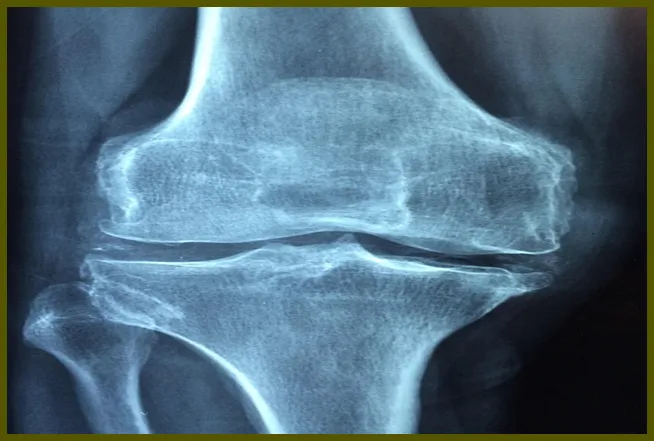

무릎 연골 손상이란?

무릎 연골은 뼈와 뼈 사이에서 충격을 흡수하고 움직임을 원활하게 만드는 역할을 합니다. 이 연골이 손상되면 여러 가지 불편함을 초래하는데, 주로 무릎의 통증, 부기 및 운동 범위 제한 등이 발생합니다. 연골 손상은 일반적으로 외부 충격이나 과도한 운동에 의해 발생합니다. 예를 들어, 농구나 축구와 같은 스포츠에서 뛰거나 이동하는 과정에서 갑작스러운 움직임이 있으면 연골이 손상될 수 있습니다.

- 퇴행성 변화: 나이가 들면서 나타나는 관절의 자연적인 변화